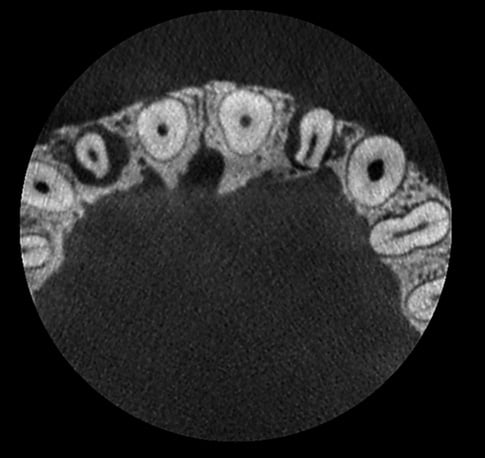

Bez redukcji szumów

Po użyciu filtra szumów Planmeca AINO

Planmeca ProMax 3D s Ø50x50 mm, rozmiar woksela 75µm

Planmeca ProMax 3D Mid Ø40x50 mm, rozmiar woksela 75µm